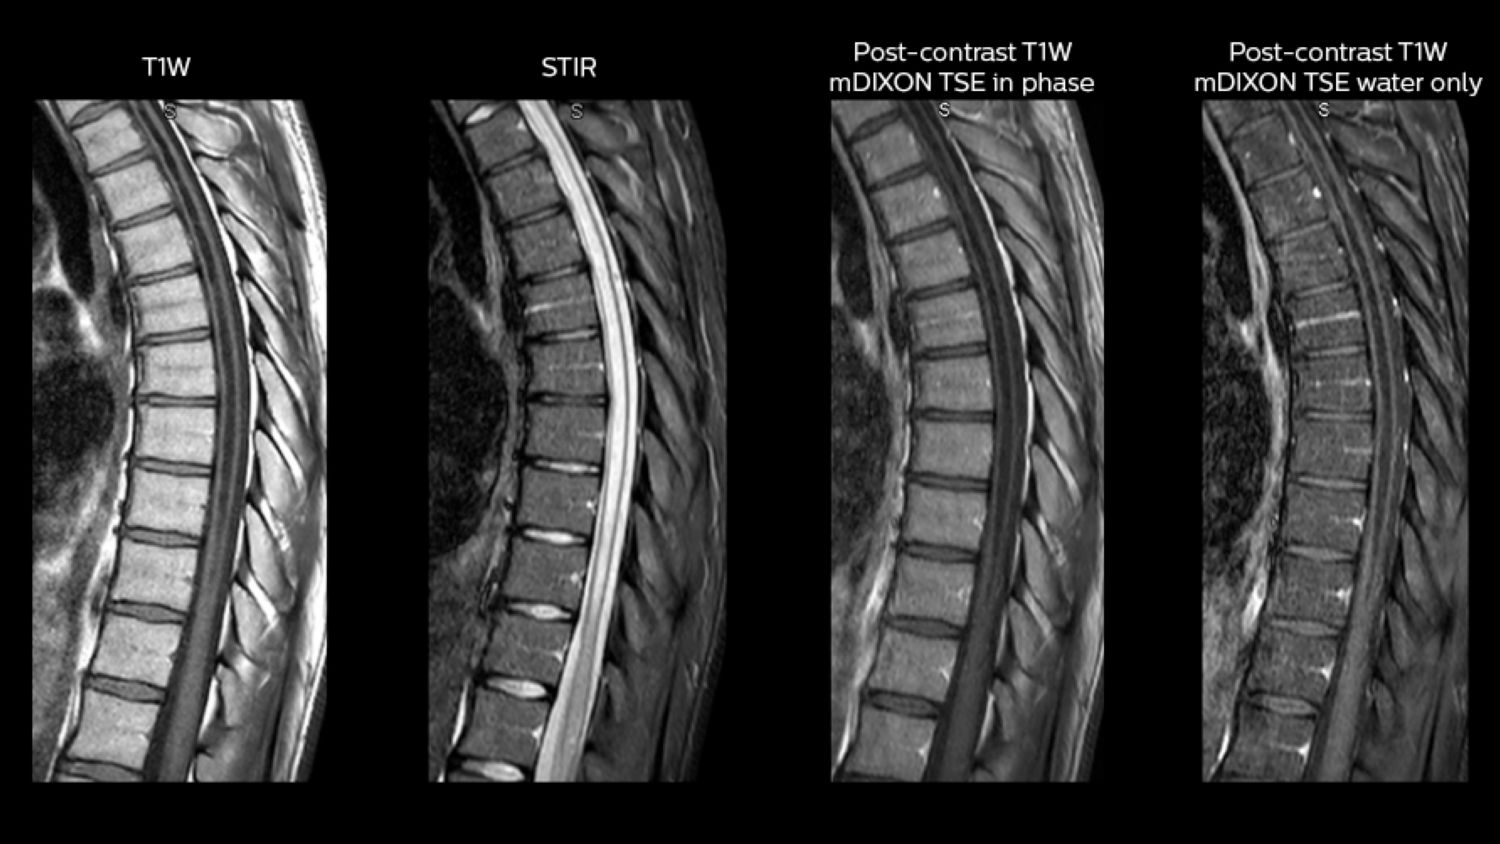

Clinical case: Myelopathy imaging: the role of mDIXON

A patient with previously resected metastatic focus from the posterior fossa, presented to the ED with new symptoms of meningismus Patients with myelopathy are recommended to get a contrast-enhanced study of the cervical or thoracic spine, depending on the level of finding. In case of myelopathy a more traditional STIR exam is used instead of T2W mDIXON because of the slightly improved contrast within the cord. mDIXON is used for post-contrast T1-weighted imaging so that water-only and fat-plus-water post-contrast T1-weighted imaging is available.

Post-contrast axial T1W and axial T2W gradient echo is then performed, targeted to areas where the tech sees a clear finding in the patient in order to keep the scan time short. Performed on Ingenia 1.5T.

mDIXON in myelopathy imaging